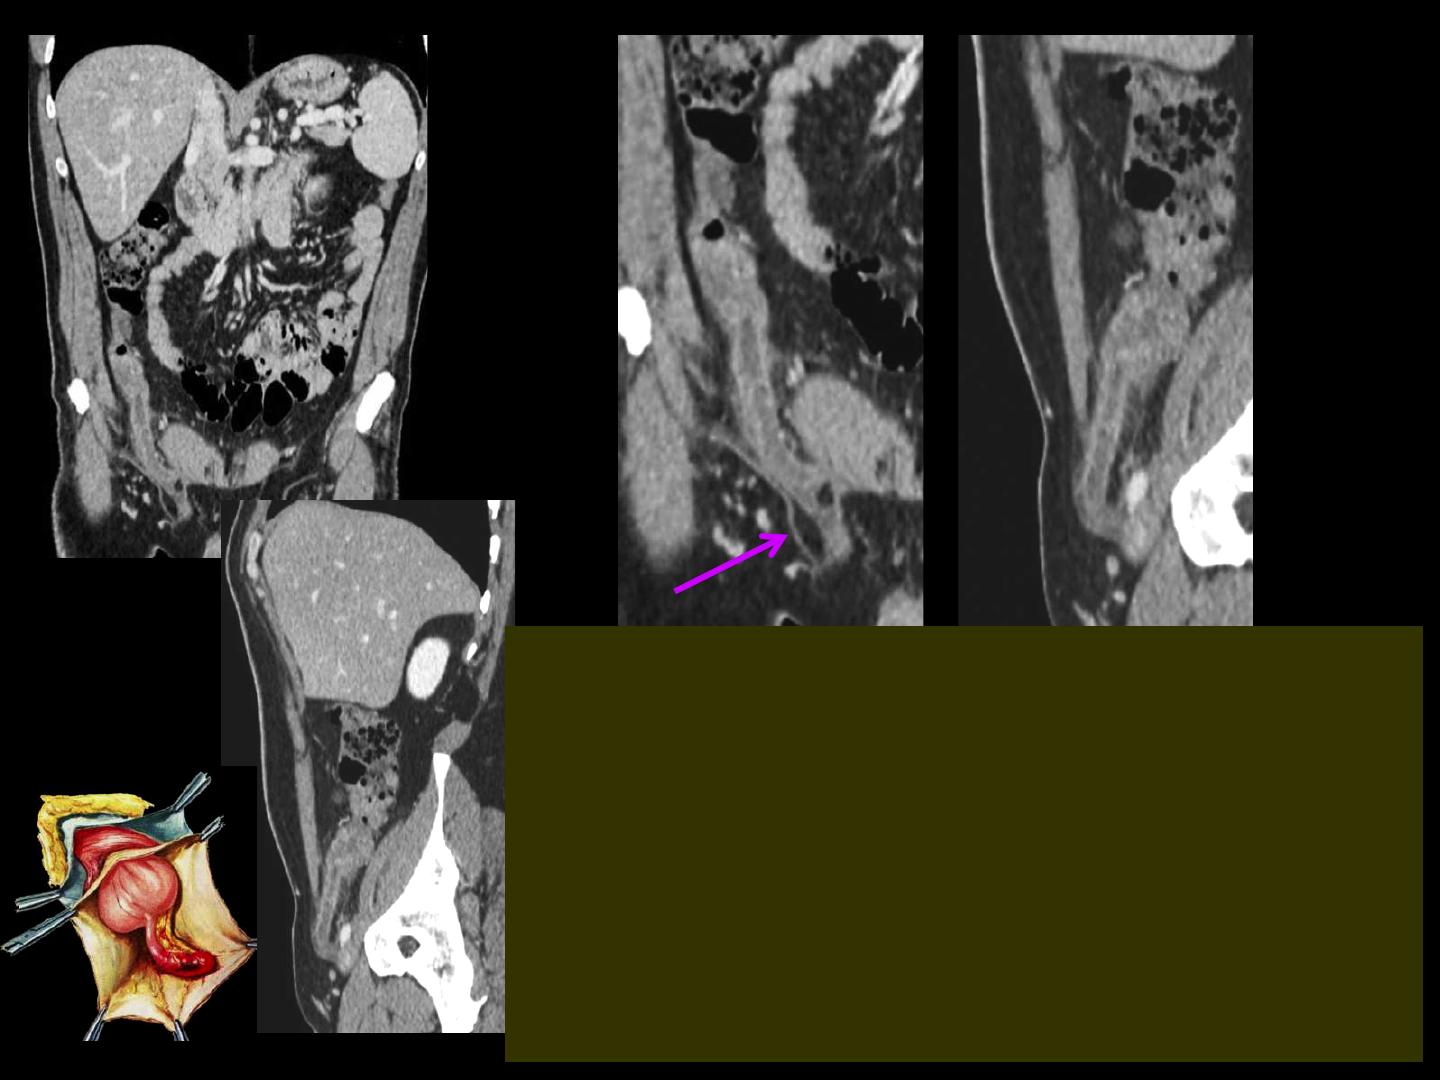

-chez l'adulte le diagnostic de hernie de Claudius

Amyand peut être une découverte d'imagerie. La

fréquence des hernies de Claudius Amyand chez

l'adulte a été de 0,4 % dans une série récente de

963 patients grecs opérés pour hernie inguinale. En

cas d'appendicite herniaire et surtout si le

diagnostic est retardé chez des sujets âgés la

présentation peut être celle d'un abcès de l'aine .

abcès de l'aine compliquant une appendicite

sur hernie de Claudius Amyand !